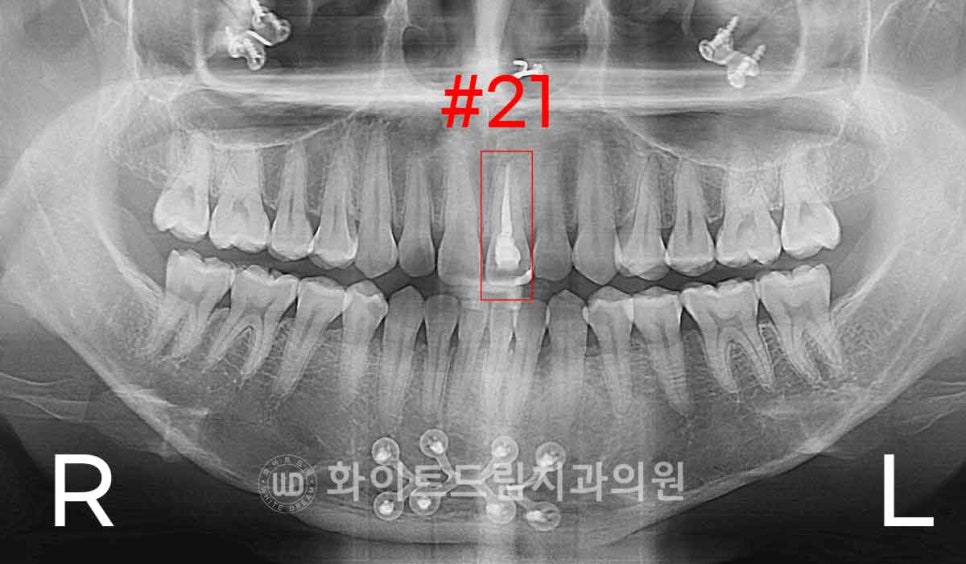

환자분의 X-ray 사진을 함께 살펴보면,

이 치아는 단순히 표면에 착색이 묻은 정도가 아니라

치아 내부에서부터 점차 색이 어두워지는

전형적인 ‘신경치료 후 변색’ 패턴이 나타나고 있었습니다.

▲ 신경치료가 되어있는 21번 앞니 / 강남역앞니치과